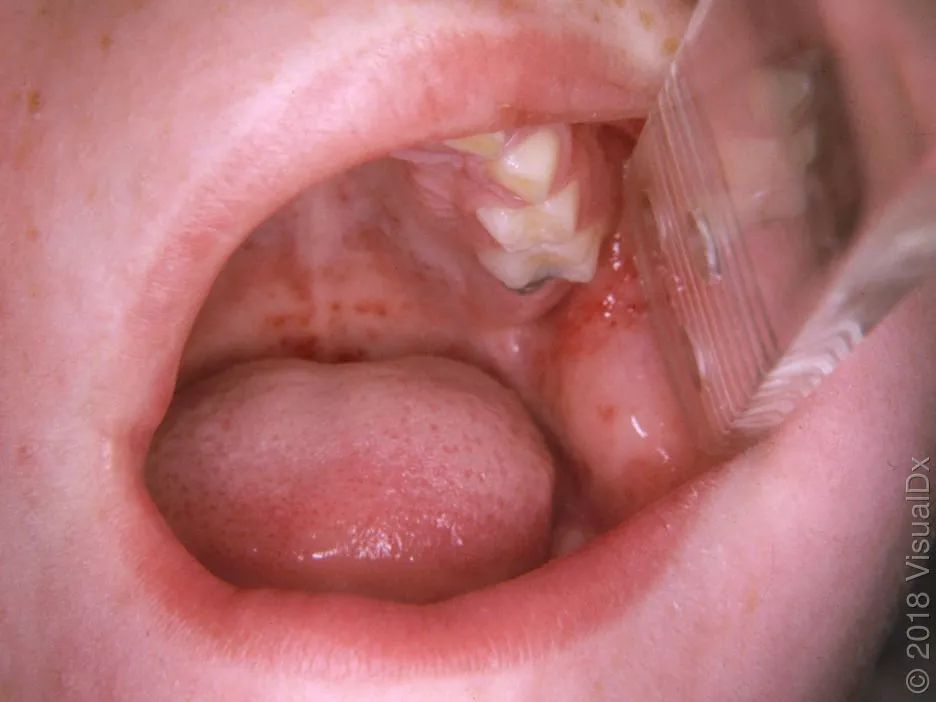

这时如果检查孩子的咽喉处,开始时能看到上颚处有红色点状出血疹,之后能看到咽部和软腭、扁桃体有白色斑片渗出,这种斑片容易擦掉,如下图所示:

上图左侧是软腭处的出血点,右图能看到白色分泌物